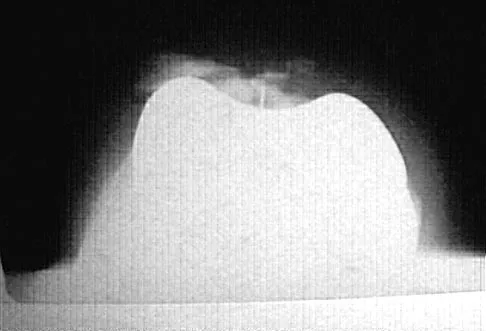

A 72-year-old woman who is right hand-dominant has severe pain in the right shoulder that has failed to respond to nonsurgical management. She reports night pain and significant disability. Examination reveals 30 degrees of active forward elevation. An AP radiograph is shown in Figure 27. Which of the following treatment options will provide the best functional improvement?

Explanation